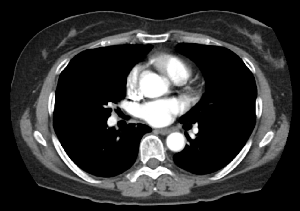

전신용 (Fan Bim CT) CT

전신(Whole Body)의 검사가 가능한 CT 장비입니다.

신체의 모든 부위를 검사하는 용도로 사용됩니다.

대부분의 상급종합병원, 종합병원, 병원, 의원에서 사용되고 있습니다.